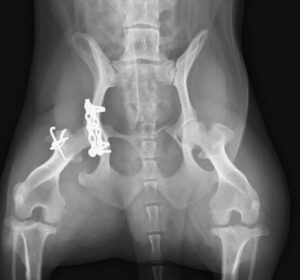

交通事故で当院夜間救急外来へ来院しました。右後肢に重度の疼痛と内出血を認め、X線検査にて複数箇所の「骨盤骨折」が見つかりました。幸い他に大きな致命傷はありませんでしたが、念の為、点滴や痛み止めを使用しながら内科治療を実施し、受傷から3日後に骨盤骨折の整復術を行いました。複雑な場所の骨折だったため、小さいプレートを駆使しながら正しい位置で固定。6週間後には元気に走り回っています。